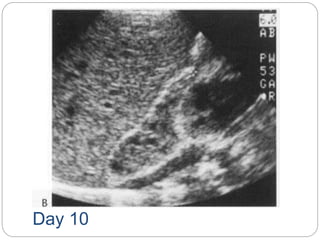

 Ultrasound in the first few days of life

usually demonstrates an avascular

heterogenous adrenal mass that

becomes cystic and smaller over the

following weeks as clot retraction occurs

Day 2

Day 10

Resolving adrenal heamorrhage commonest cause of an adrenal mass  Associated with perinatal stress, hypoxia, septicaemia and hypotension  may be unilateral or bilateral  Adrenal insufficiency is rare, even in bilateral cases.  Ultrasound in the first few days of life usually demonstrates an avascular heterogenous adrenal mass that becomes cystic and smaller over the following weeks as clot retraction occurs